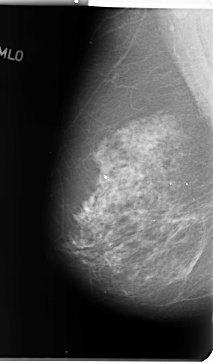

Digital Database for Screening Mammography

Volume: benign_01 Case: B-3131-1

B_3131_1.LEFT_MLO

LEFT_CC LINES 4712 PIXELS_PER_LINE 2632 BITS_PER_PIXEL 12 RESOLUTION 50 OVERLAY

LEFT_MLO LINES 4672 PIXELS_PER_LINE 2768 BITS_PER_PIXEL 12 RESOLUTION 50 OVERLAY

FILE: B_3131_1.LEFT_MLO.OVERLAY

TOTAL_ABNORMALITIES 1

ABNORMALITY 1

LESION_TYPE CALCIFICATION TYPE PLEOMORPHIC DISTRIBUTION CLUSTERED

ASSESSMENT 4

SUBTLETY 3

PATHOLOGY BENIGN

FILE: B_3131_1.LEFT_CC.OVERLAY